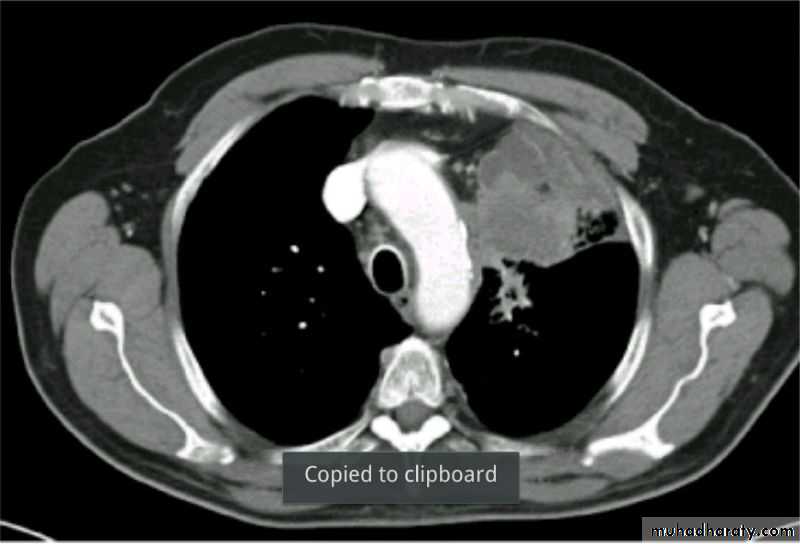

Severe dyspnea with shock

Fall from the 2nd floor